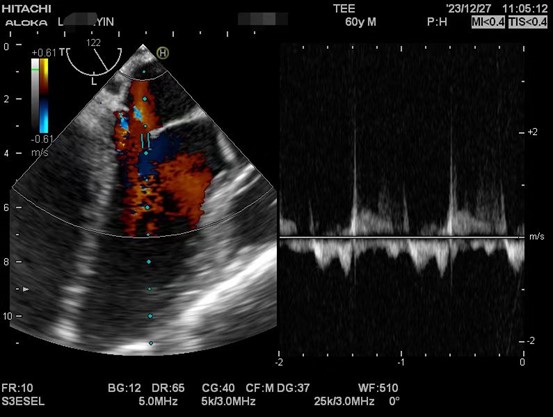

肝硬化患者术前合并症较多,术中血流动力学波动剧烈,围术期可能发生严重低血压、心内血栓形成、肺栓塞、左室流出道梗阻、心室收缩舒张功能不全等危急事件,给麻醉管理带来巨大挑战。TEE是将超声探头放在食管中段或胃底,从心脏后方持续观察心脏结构和功能,避免肺气对成像的影响,图像清晰且不影响手术的操作,是肝移植术中重要的监测手段之一。美国心脏超声协会及美国心血管麻醉医师学会均推荐肝移植术中常规使用TEE。目前美国各大移植中心术中麻醉科术中常规使用TEE进行持续监测。

以下是肝移植术中TEE监测的图像。